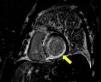

A case of cardiogenic shock with preserved ejection function

Un caso de shock cardiogénico con función de eyección conservada